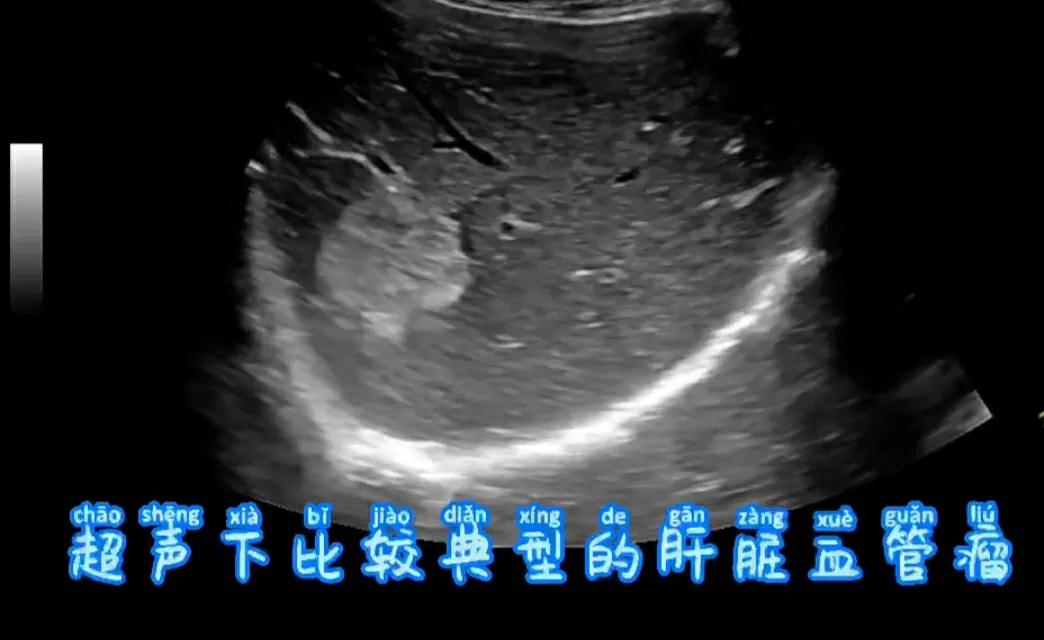

超声是临床上检查肝血管瘤最常用的一种影像学方法,可以有对肝血管瘤进行诊断和鉴别诊断。肝血管瘤的B超表现为高回声,部分呈低回声,当部分血管瘤呈低回声表现时,不易于早期肝癌区别,可采用超声血管造影或CT扫描检查进行鉴别诊断。

肝血管瘤为肝脏的良性肿瘤,较小且无临床症状的肝血管瘤可以定期观察,动态检测血管瘤大小变化等。肝血管瘤在超声扫描动态观察下,血管瘤往往长期形态大小无改变;当肝血管瘤较大时可出现压迫症状,引起上腹痛、阻塞性黄疸、胃肠道不适等临床表现,因此大于5cm的血管瘤建议咨询临床医生,及早进行相关治疗。